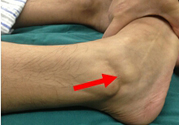

韌帶斷裂后,如果不能徹底治愈康復(fù),以后關(guān)節(jié)就會(huì)出現(xiàn)彎曲受限等不適現(xiàn)象,早期一般都會(huì)有僵硬拉扯感、關(guān)節(jié)彎曲活動(dòng)受限制等癥狀。